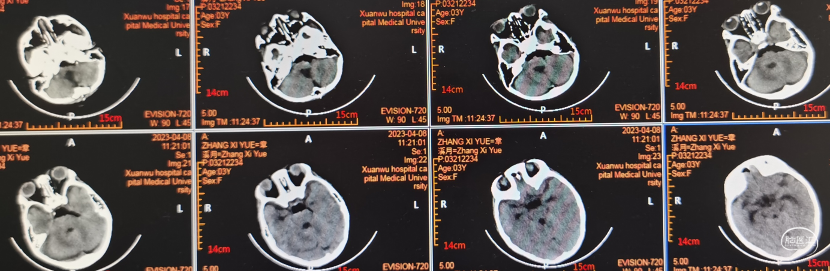

术前影像学检查

CT